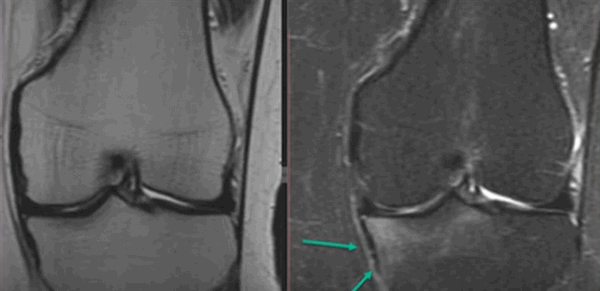

МР-скан коленного сустава в Т1 режиме (стрелкой указан костный отек)

МР-снимок коленного сустава в режиме Т2, контузия кости